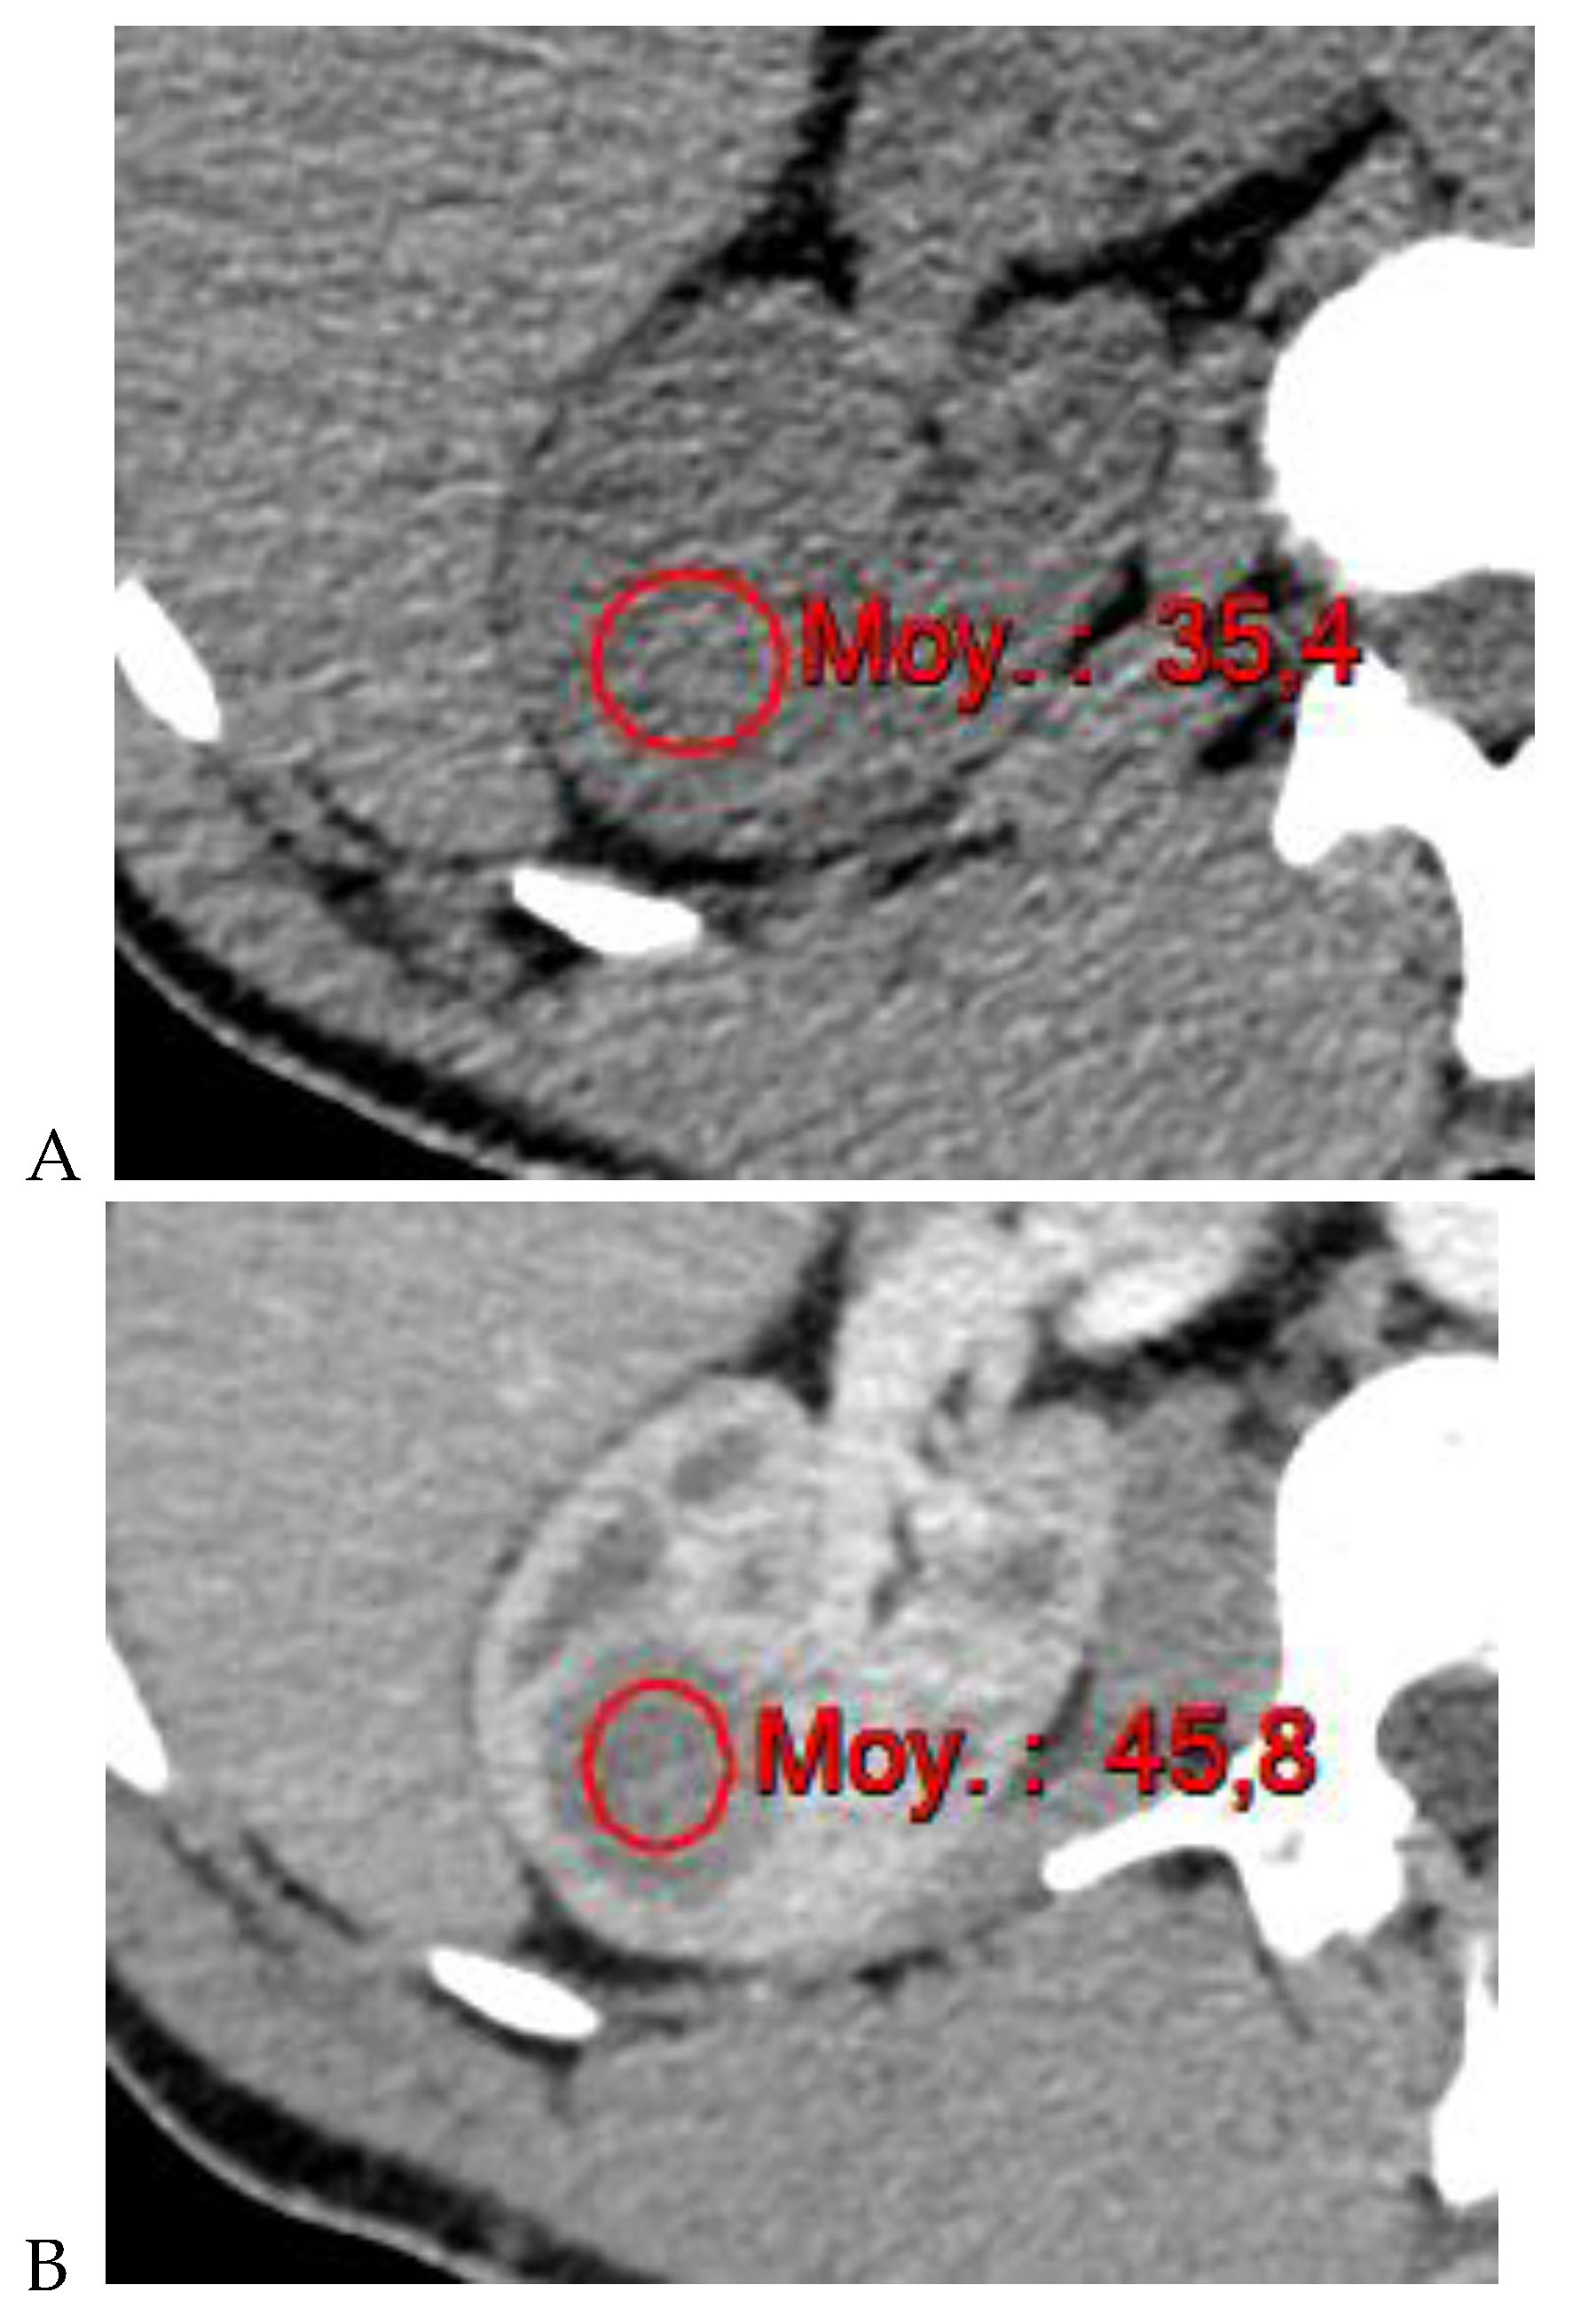

Figure 4.

Multiphasic CT enhancement of a papillary renal cell carcinoma in the middle part of the right kidney of a 63-year-old woman. (A) Mean unenhanced attenuation was 35 HU. (B) Mean corticomedullary phase attenuation was 45 HU. (C) Mean nephrographic phase attenuation was 59 HU. (D) Mean excretory phase attenuation was 65 HU.

Along with unenhanced images, enhancement on multiphasic CT provides a simple, noninvasive means of suggesting the histologic type of a renal mass. It is defined by an increase of 20 HU or more between precontrast and contrast-enhanced images [11]. In daily practice, an enhancement of <10 HU is considered to be characteristic of a cyst, 10–19 HU of an indeterminate mass, and >20 HU suggestive of a renal tumor. Young et al. [9] showed that the mean enhancement of clear cell RCC (Figure 1) was significantly greater than that of oncocytoma (Figure 2) and chromophobe RCC (Figure 3) in the cortico-medullary and excretory phases, and significantly greater than that of papillary RCC (Figure 4) in the cortico-medullary, nephrographic, and excretory phases. In their series, the mean attenuation values during the corticomedullary phase were 125.0 HU for RCCs, 106.0 HU for oncocytomas, 53.6 HU for papillary RCCs, and 73.8 HU for chromophobe RCCs. However, this quantitative information does not necessarily translate into clinically meaningful measures in daily practice due to the variability and overlap in HU measurements. In a recently published study of 87 patients with 93 pathologically proven papillary RCCs [31], most papillary RCCs presented as a hypovascular, circumscribed, solid renal mass; a few (17%) papillary RCCs presented as the newly defined Bosniak class IIF subtype.